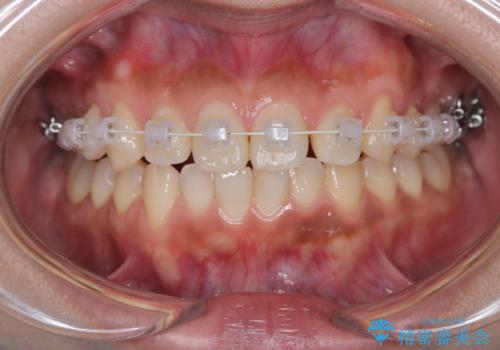

臼歯部の反対咬合を改善|MARPEによる上顎急速拡大+審美ワイヤー矯正

- 患者様は、奥歯(臼歯部)の反対咬合を主訴に来院されました。反対咬合は、噛み合わせのズレや顎の成長に影響を与える可能性があるため、早期の治療が重要です。診断の結果、上顎の幅が不足していることが原因と判明し、MARPE(骨固定式上顎急速拡大装置)を用いて上顎を広げる治療を計画しました。その後、歯列の調整のために審美ワイヤー矯正を行う方針としました。

MARPEを使用して上顎を拡大し、適切な歯列のスペースを確保しました。この拡大によって、反対咬合が改善され、正常な噛み合わせへと誘導できました。その後、目立ちにくいブラケットと白いワイヤーを使用した審美ワイヤー矯正を行い、歯列を整えました。治療が進むにつれ、噛み合わせのバランスが良くなり、見た目も自然な仕上がりに。